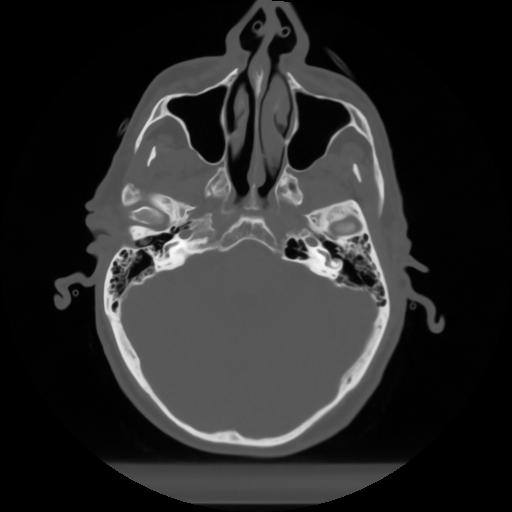

10 P.BLANDAS,,Axial,2.0,P.BLANDAS,,